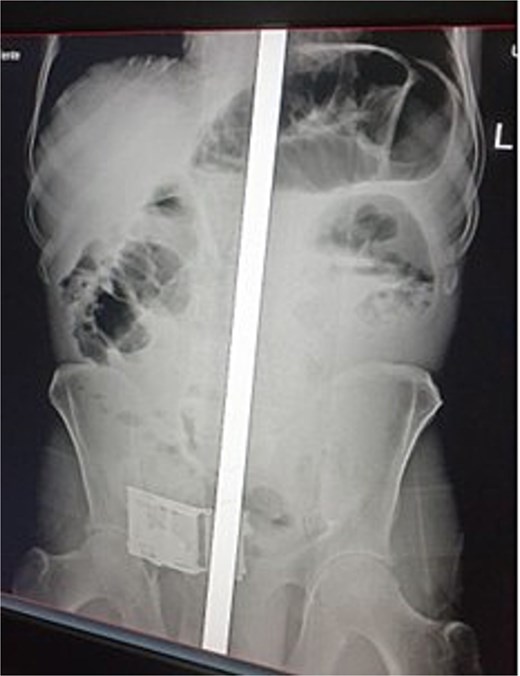

On examination, his vital signs were within normal limits. His abdomen was slightly distended with visible dilated bowel loops but no tenderness. A rectal examination revealed a collapsed, empty rectum. A plain abdominal X-ray showed visible dilated bowel loops (Fig. 1). Blood tests revealed normal complete blood count and organ function tests. An abdominal CT scan was not performed due to the temporary unavailability of the CT scanner.

Abdominal radiograph showing multiple distended loops of small bowel.